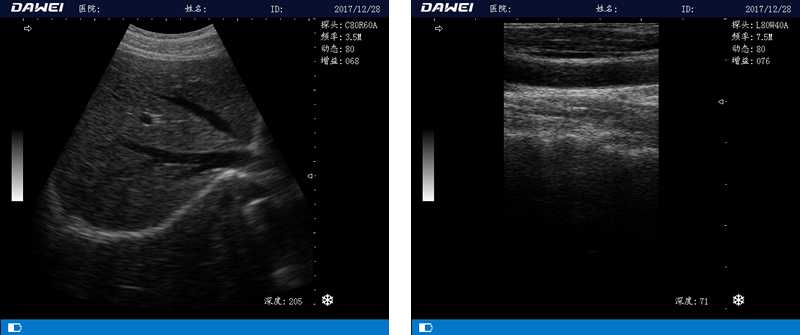

筆記本全數字超聲診斷儀

1.優(yōu)質的數字成像技術,圖像更清晰

5.體積小巧,圖像清晰,操作方便,續(xù)航能力強